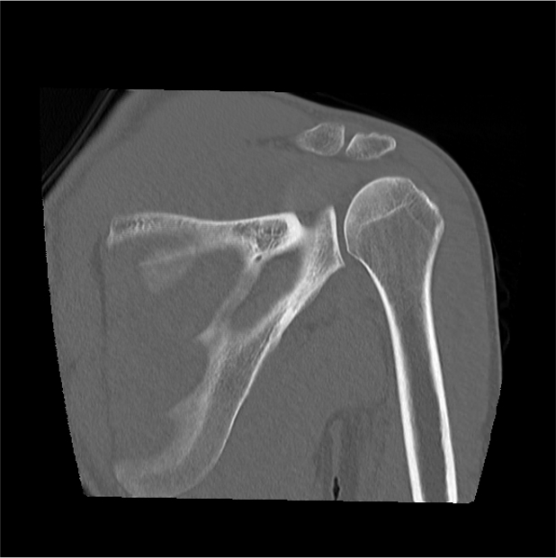

- Coronal, sagittal and axial images in both soft tissue (WW:500, WL:50) and bone (WW: 3500, WL: 350) window with ≤2mm slice thickness.

- 3d images to show pathologies clearly.